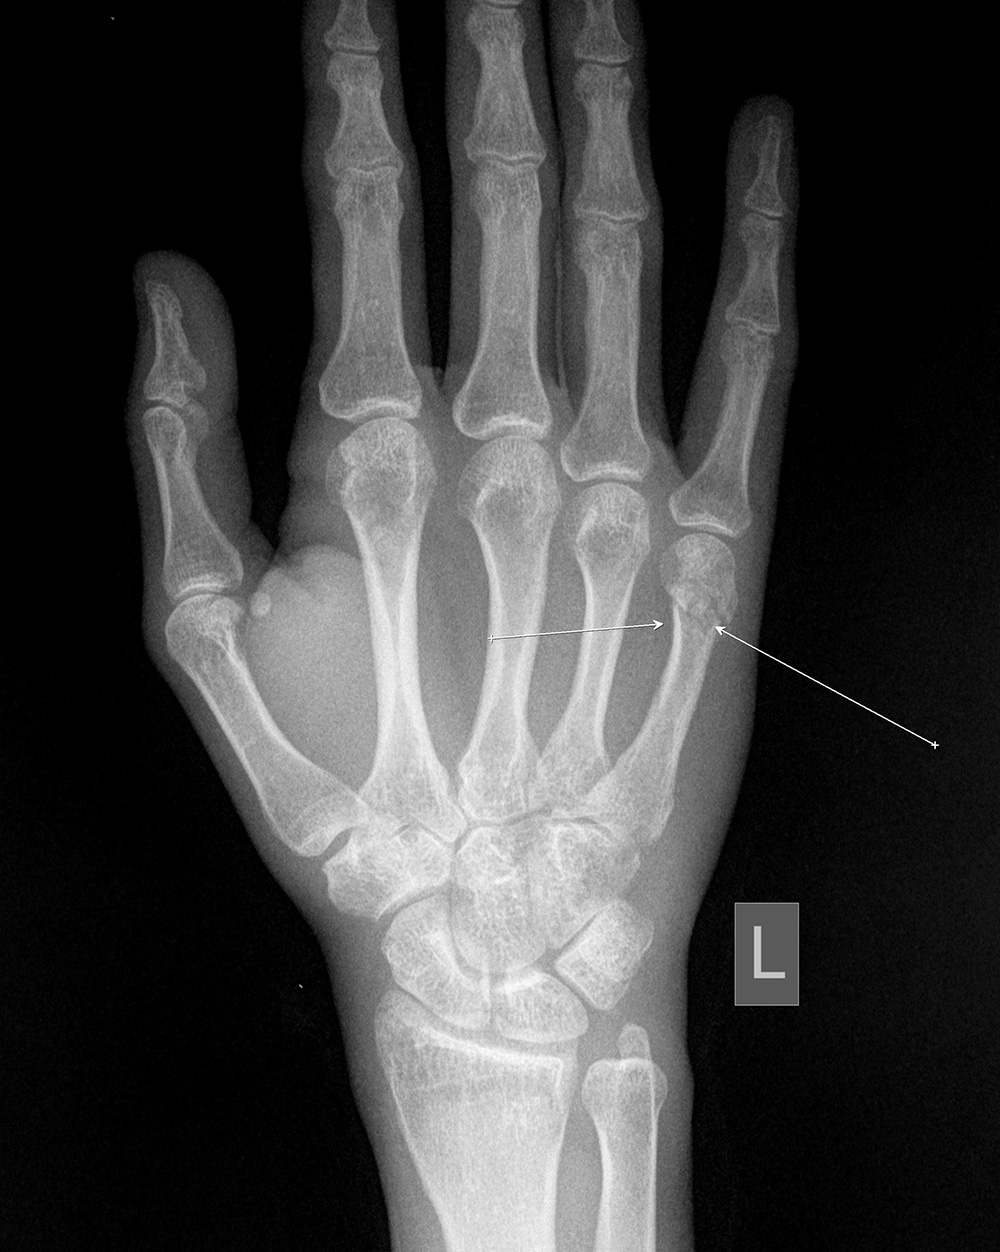

На рентгенограмме левой кисти в 2-х проекциях - околосуставной остеопороз с участками кистозной перестройки, в области дистального метафиза 5-ой пястной кости имеется не полностью сопоставленный, слабо консолидированный перелом, лучезапястный сустав - межсуставная щель сохранена, суставные поверхности с ровными контурами, умеренный субхондральный остеосклероз.

5. Рентгенография кисти- в области метафиза 5-ой пястной кости имеется перелом со смещением костных отломков